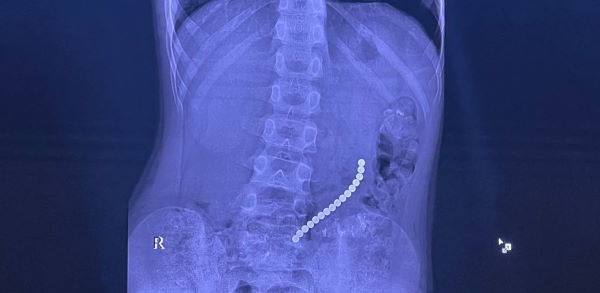

В Иркутске врачи спасли ребёнка, проглотившего 16 шариковых магнитов

В Иркутской областной детской клинической больнице спасли жизнь восьмилетнего пациента, который проглотил шариковые магниты.

Ребёнок поступил с болями в животе. Инородные тела вызвали повреждение желудочно-кишечного тракта. Несколько магнитов соединились между собой в различных сегментах внутренних органов.

- Очень редкое сочетание: одни магниты находились в желудке, другие — в начальном отделе тонкой кишки. Это привело к образованию фистулы — сообщению между желудком и кишкой. Мы использовали технологию минимально-инвазивной хирургии, чтобы разделить органы и восстановить их целостность после извлечения инородных тел, - пояснил главный врач больницы, знаменитый детский хирург Юрий Козлов.